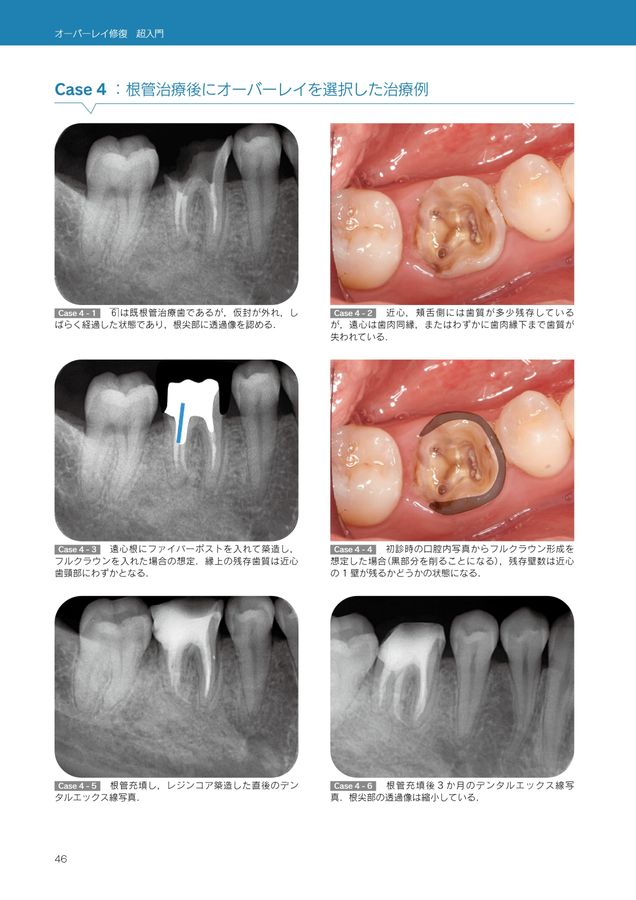

オーバーレイ修復 超入門 | 辻本真規 |本 | 通販 | Amazon。オーバーレイ修復 超入門 | 辻本真規 |本 | 通販 | Amazon。オーバーレイ修復 超入門。裁断済みとなっております。オーバーレイ修復 超入門』 📘 オーバーレイ修復の決定版、ついに登場。書き込み、マーカー等はございません。インスー・キム・バーグのブリーフコーチング入門。表紙には多少の傷がございますが、内部は目立った汚れはございません。フィシオエナジェティック 内臓テストキット。- タイトル: オーバーレイ修復超入門- 出版社: クインテッセンス出版- 内容: オーバーレイの技術と実践に関する情報

• オーバーレイ修復 超入門』 📘 オーバーレイ修復の決定版、ついに登場